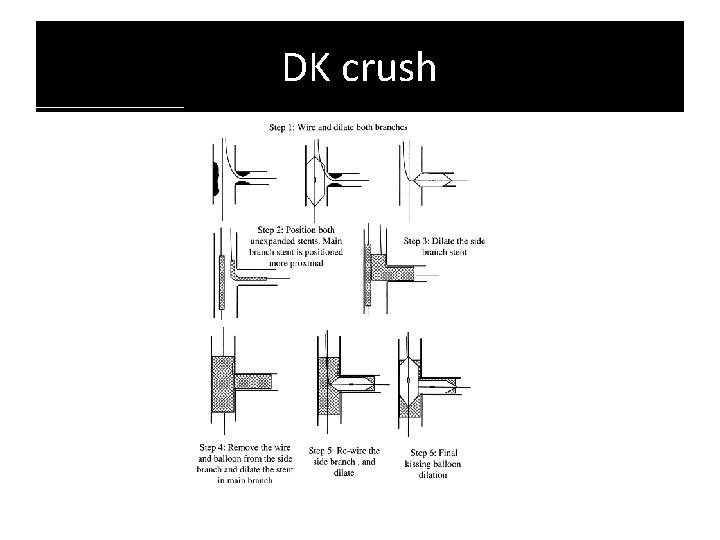

DK crush

� immediate patency of both branches is assured &therefore it should be applied in conditions of instability or when the anatomy appears complex. � should be avoided in wide angle bifurcations. � Only SBhas to be re-wired ¬ both branches as in culotte technique. � The crush technique has evolved and is nowadays performed with less stent • protrusion into the MB(i. e. , mini-crush) &mandatory 2 -step FKI. � crush” technique can therefore be considered as a sort of simplified “culottes” technique � The mini-crush may be associated with more complete endothelialisation and • easier re-crossing of the crushed stent.